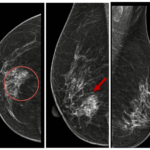

CASE LÂM SÀNG Điều trị bệnh nhân mắc đồng thời hai loại ung thư: Ung thư phổi và ung thư tuyến tiền liệt

CASE LÂM SÀNG Điều trị bệnh nhân mắc đồng thời hai loại ung thư: Ung thư phổi và ung thư...